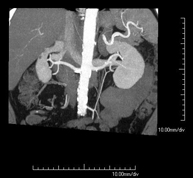

- Angio-TC arterias renales

Prueba diagnóstica no invasiva que consiste en el estudio de las arterias renales obteniendo imágenes de alta definición anatómica mediante el empleo de un equipo de TC (Tomografía Computarizada) y de contraste yodado. La calidad de las imágenes permite realizar reconstrucciones en 2D y 3D gracias a estaciones de trabajo especializadas en el estudio arterial. Esta prueba está indicada, por ejemplo, en aquellos pacientes que sufren de HTA refractaria al tratamiento, en pacientes con lesiones renales para tener un mapa "vascular" pre-quirúrgico, etc.